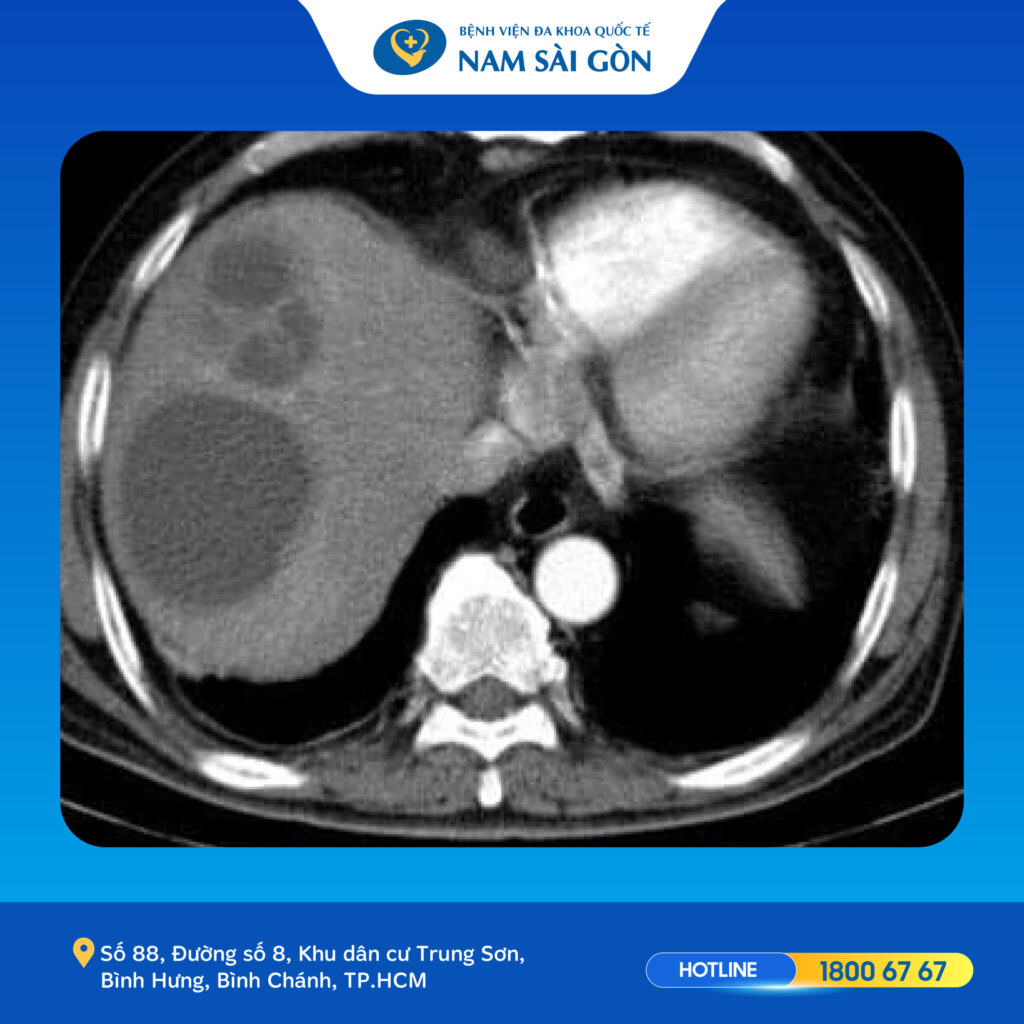

អ្នកជំងឺត្រូវបានបញ្ជូនមកមន្ទីរពេទ្យក្នុងស្ថានភាពអស់កម្លាំងខ្លាំង គ្រុនក្តៅខ្លាំងរយៈពេល 8 ថ្ងៃជាប់ៗគ្នានិងរាក។ បន្ទាប់ពីការពិនិត្យ និងការធ្វើតេស្តបឋមជាចាំបាច់ លទ្ធផលតេស្តបានបង្ហាញពីសន្ទស្សន៍នៃការឆ្លងមេរោគខ្ពស់កោសិកាឈាមសដែលមានប្រតិកម្មហើយក្នុងពេលជាមួយគ្នានោះវេជ្ជបណ្ឌិតបានរកឃើញអាប់សថ្លើមធំៗពីរដុំដែលមានទំហំ 8×6 សង់ទីម៉ែត្រ និង 4×5 សង់ទីម៉ែត្រ។